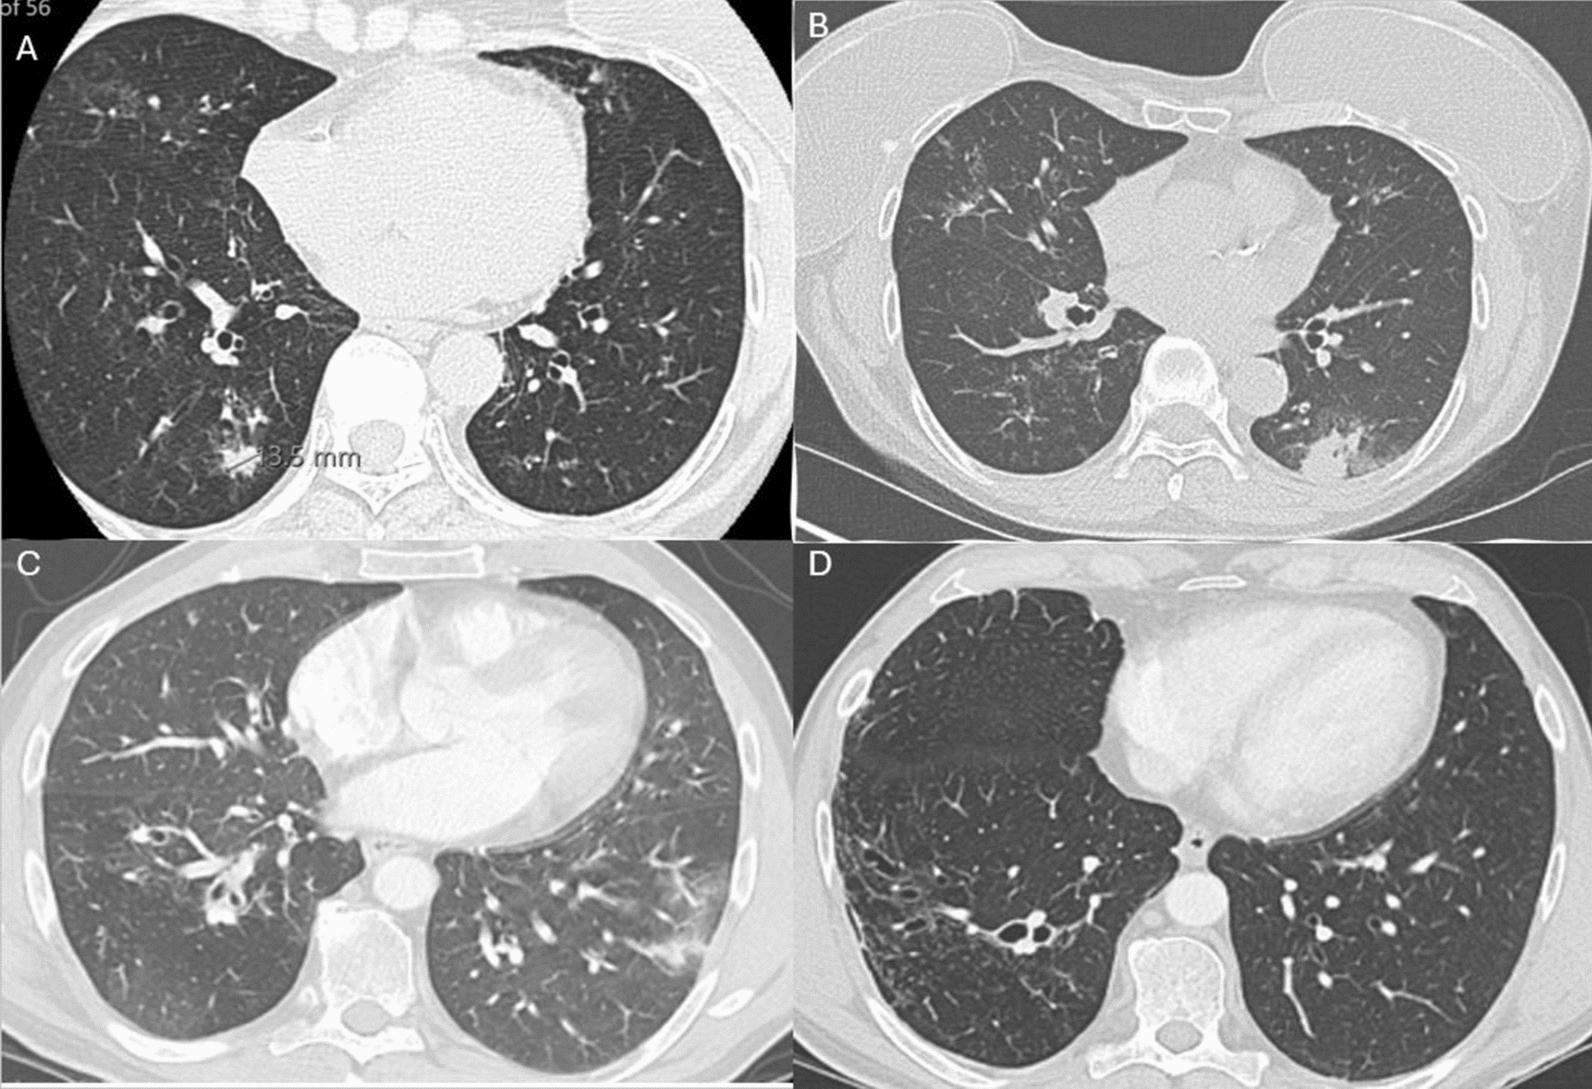

Background: Allergic bronchopulmonary aspergillosis (ABPA) presents with a wide range of symptom severity, with severe disease manifestations being harder to control through conventional inhalers. While corticosteroids remain a standard treatment option, their use is often hindered by significant adverse side effects. This case series discusses a novel treatment of duo-administration of monoclonal antibodies for two patients that reduced their exacerbations, spared the use of steroids, and improved their quality of life.

Case presentation: Both patients were diagnosed with ABPA. Before the administration of treatment, they experienced almost monthly exacerbations and infections requiring constant systemic oral corticosteroids and antibiotics. After the implementation of successive concomitant monoclonal antibody treatments, absolute eosinophil levels were brought down to normal levels, and the monthly exacerbations were eliminated.